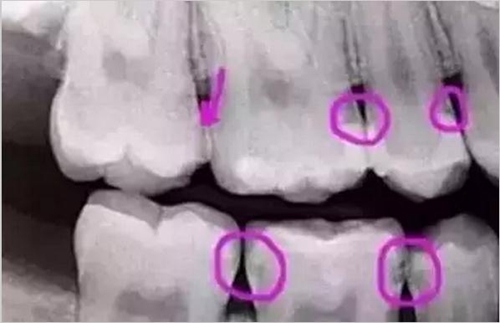

圈出來的地方或多或少都有點齲齒,但是有些你并不能看見。這些齲齒還淺不會讓你有什么感覺,頂多吃東西塞牙,和冷水敏感而已。